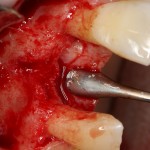

Сначала фиксируется BioGide. Это легко:

Затем укладывается и конфигурируется аутокостная стружка: